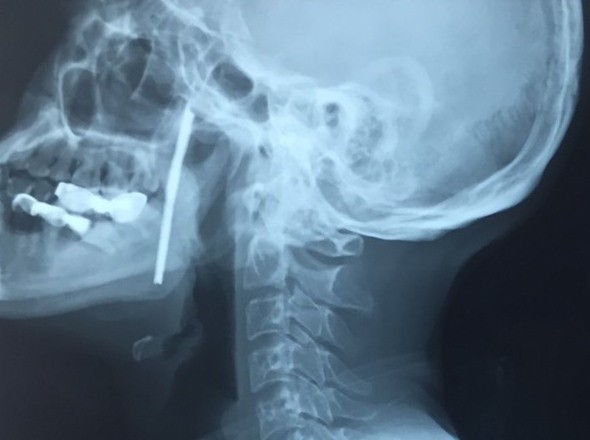

Bệnh viện Hữu nghị Việt Đức cho biết, bệnh nhân L.V.T., 40 tuổi, sống ở Sơn La bị một thanh sắt dài 10 cm cắm vào chính giữa vùng cổ trong lúc lao động.

Ngay sau khi tiếp nhận bệnh nhân, TS. Vũ Ngọc Tú - Trung tâm Phẫu thuật Tim mạch và Lồng ngực, Bệnh viện Hữu nghị Việt Đức – chẩn đoán bệnh nhân bị vết thương phức tạp vùng cổ do thanh sắt kim loại dài, xiên từ hầu họng vào trong miệng - là vùng có rất nhiều cơ quan hệ trọng của cơ thể như đường thở (khí quản), đường ăn (thực quản), các mạch máu nuôi não (động mạch cảnh).

May mắn, thanh sắt chưa trực tiếp gây tổn thương các vùng quan trọng của cơ thể nhưng lại nằm sát cạnh các vùng đó. Vì thế, các bác sĩ phải lấy bằng được dị vật nhưng vẫn đảm bảo an toàn tuyệt tính mạng người bệnh, đồng thời, giữ được các chức năng của cơ thể.